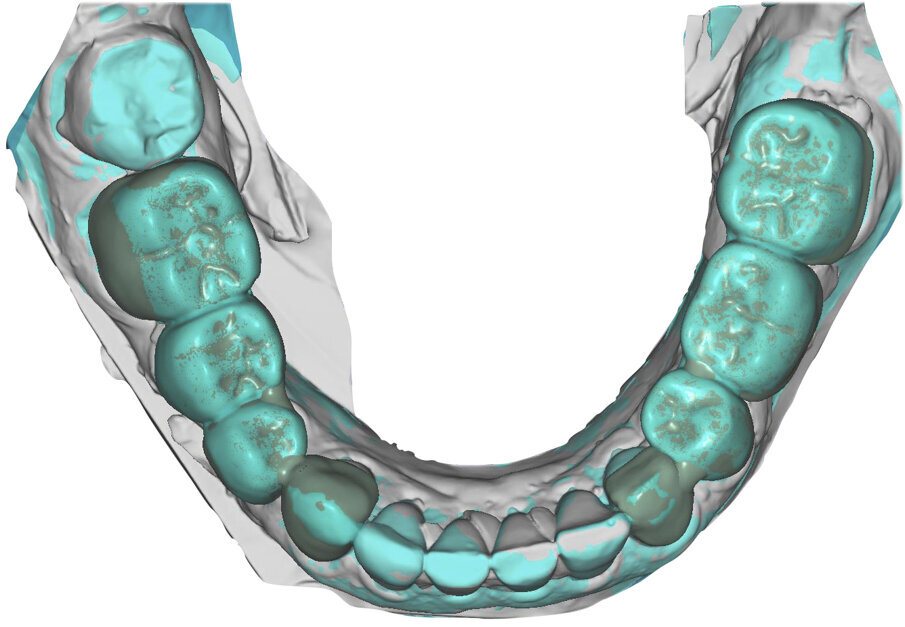

I modelli sono così importati in corretta posizione spaziale tramite il modulo exocad Virtual Articulator (Fig. 25). Non avendo a disposizione nel CAD l’analogo virtuale dell’articolatore Reference SL, viene impostato il sistema virtuale SAM, che usa lo stesso piano di riferimento axio-orbitale e geometria sovrapponibile al Reference SL. Per la programmazione virtuale dei parametri funzionali dell’articolatore si riesegue l’output dall’axiografia elettronica con Gamma Dental per SAM (Fig. 26). Si procede perciò ora con la modellazione CAD della ceratura mantenendo il riferimento dato dal piano occlusale individuato dai coni di centrica scansiti con l’articolatore (Fig. 27). L’articolatore virtuale consente una prima verifica dei rapporti occlusali tra gli elementi e un abbozzo di funzionalizzazione delle cuspidi con strumenti virtuali dinamici, che permette di arrivare ad un CAD design vicino alla morfologia ricercata (Figg. 28-33). Il modellato è ora fresato in cera Yeti Dental al CAM con fresatore VHF Cam5-S1 ed i denti in cera, tutti singolarmente sfilabili, sono posizionati sui modelli eseguiti con stampa 3D.

Il fresato ottenuto è poi riportato su articolatore Reference SL – già opportunamente programmato – e viene dall’Odontotecnico competente più precisamente funzionalizzato secondo i criteri della programmazione funzionale sequenziale, evidenziando con cere colorate i rapporti di centrica, le funzioni di mediotrusiva e protrusiva e le protezioni retrusive. I monconi sfilabili consentono la modellazione della sequenzialità mediotrusiva con la guida incisale indicata dalla registrazione axiografica (blu) (Figg. 34-37). La ceratura sequenziale è ora scansita con Sirona InEos X5 su Exocad, ed il modellato viene ricontrollato al CAD per spessori, connessioni e morfologia, e nella regolazione degli offsets per la ripreparazione dei monconi, ed è inviato al CAM per la fresatura dei II provvisori in Bredent breCAM.multicom, un PMMA con microriempitivo ceramico ad alta stabilità, su Dental Plus 5 Axis Milling Machine. La rifinitura dei monconi è seguita da ribasatura dei II provvisori in TRP - previo isolamento di tutte le superfici funzionali - e gli stessi sono poi rifiniti e lucidati. I soli elementi 3.3, 4.2 e 4.3 sono rimodellati in regione incisale con addictions in composito, secondo la morfologia studiata in ceratura. La consegna conferma la buona integrazione dei manufatti dal punto di vista estetico, occlusale, articolare e neuromuscolare, con controllo occlusale conforme al progetto (Figg. 38-42).

Il paziente utilizza questi secondi provvisori per otto settimane, durante le quali conferma la buona integrazione dei restauri e la soddisfacente funzione occlusale. Ciò è verificato con l’esecuzione di una nuova axiografia elettronica che già a due settimane dalla consegna evidenzia una buona risposta muscolare al nuovo design occlusale ed alla nuova postura mandibolare in TRP (Figg. 43-46). Provvediamo infine alle impronte per la costruzione dei manufatti definitivi in Zirconia-ceramica. I modelli sono scansiti in laboratorio con inEos X5 (Dentsply Sirona) su exocad (Figg. 47-49), ed una seconda scansione viene eseguita con i provvisori del Paziente posizionati sui modelli (Figg. 50-52). Il CAD consente di eseguire un matching fra le due scansioni, per cui i secondi provvisori utilizzati in TRP, con funzione occlusale sequenziale già completamente programmata, sono utilizzati per definire le morfologie dentali definitive di tutti gli elementi da restaurare (Figg. 53, 54) secondo il rapporto intermascellare definito (Figg. 55-58). Si esegue quindi fresatura al CAM della protesi definitiva in zirconia (Figg. 59, 60), la stratificazione e finitura ed infine la consegna al Paziente con cementazione in Panavia V5 (Figg. 61-65).